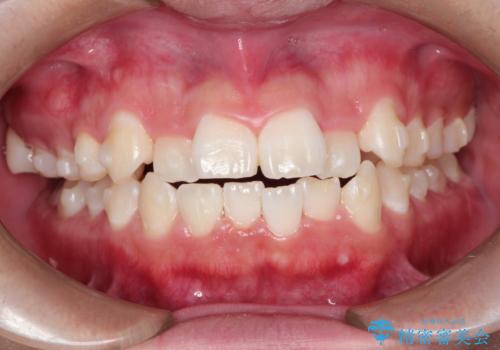

前歯のガタガタを目立たずきれいにしたい インビザラインによる見えない矯正

- 前歯のがたつきを主訴に来院されました。

上顎の前から2番目の歯の噛み合わせが反対になっていました。

抜歯矯正も考えられるケースでしたが、非抜歯での矯正を希望され、インビザラインにて治療することとなりました。

目立たずに矯正を終えることができ、患者様にも満足していただきました。